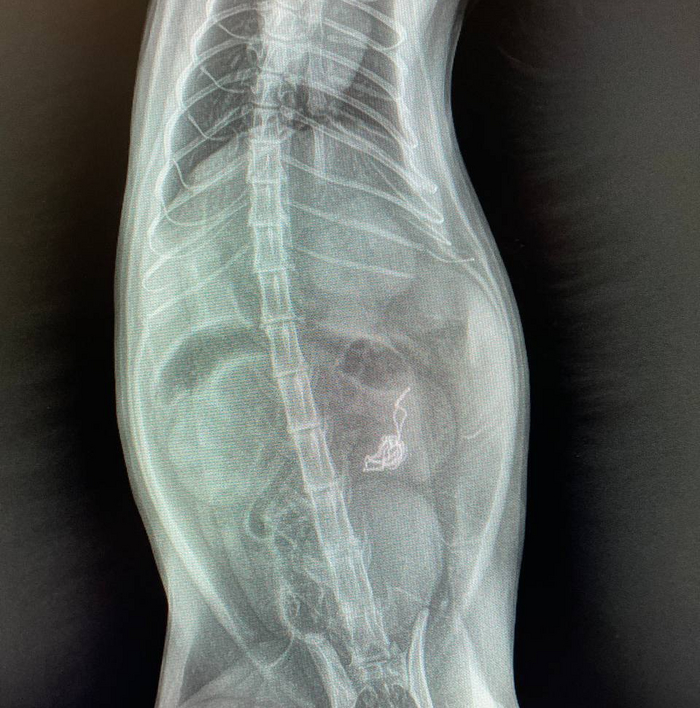

Делаем рентген.

Мы видим сломанные рёбра и изменение структуры кожи/подкожного жира, что подтверждает наличие там воздуха.

Снимок не идеальный, но позволяет увидеть наличие пневмоторакса - свободного газа в грудной полости.